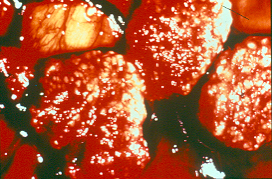

Door verworpen vrucht(en) en placenta’s van herkauwers in te sturen, kunnen op de cotelydonen van de nageboorte kleine witte necrosehaardjes worden gezien. Bij microscopisch onderzoek van de hersenen van de verworpen vrucht kunnen weefselcysten worden aangetoond. Met behulp van een specifieke immuunhistochemische kleuring (IHC) of polymerase chain reaction (PCR) kan de diagnose worden bevestigd.

Detail van de nageboorte (let op de witte stippen op de karunkels)

Weefselcyste